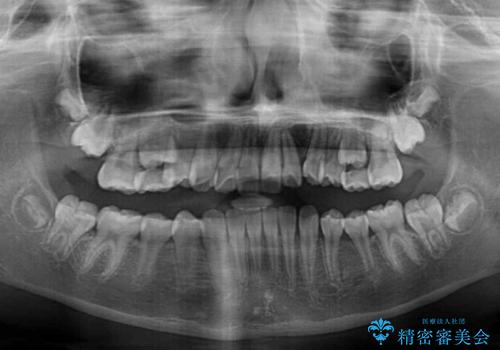

今後残っている乳歯が抜け、永久歯が萌出してくるため、調整可能なリンガルアーチを用いて保定を行っています。

12歳臼歯が萌出するまで経過観察を行い、すべての歯が萌出した後に、全顎矯正治療(Ⅱ期治療)を行っていきます。